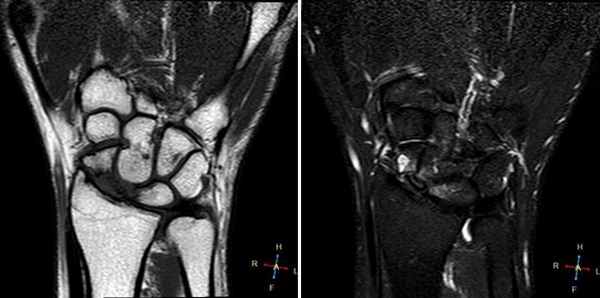

(Слева) Рентгенография левого лучезапястного сустава в ПЗ проекции: повышение плотности полулунной костив. Нет потери высоты и фрагментации. Признаки соответствуют II стадии болезни Кинбека.

(Справа) Фронтальная Т1ВИ МР-И: неоднородный гипоинтенсивный до темного сигнал в полулунной кости. Темный сигнал соответствует склерозу/фиброзу при прогрессировании заболевания. Структурные изменения визуализируются и на других изображениях, что указывают на III стадию болезни Кинбека. (Слева) Рентгенография в ЗП проекции: неоднородный склероз полулунной кости со значительным коллапсом проксимальной суставной поверхности. Несмотря на выраженные изменения, было выполнено укорочение лучевой кости. Операция выполнена для коррекции отрицательного локтелучевого индекса в попытке уменьшения механической нагрузки на деформированную полулунную кость.

(Справа) Рентгенография в ЗП проекции, этот же пациент после лечения по поводу хронического болевого синдрома. Полулунная кость была резицирована и выполнен ограниченный (головчато-крючковидный) остеосинтез. (Слева) Фронтальная Т2ВИ FS МР-И: I стадия болезни Кинбека. Отрицательный локтелучевой индекс. Отек костного мозга в полулунной и головчатой костях. Отек головчатой кости возможен на фоне нарушения осевой механической нагрузки вследствие короткой локтевой кости.

(Справа) Фронтальная T1 ВИ МР-И, этот же пациент: отек костного мозга в полулунной кости. Главная ось нагрузки проходит от лучевой кости к полулунной и головчатой до среднего пальца, ее легко оценить. Нормальная рентгенологическая картина говорит о I стадии маляции полулунной кости.